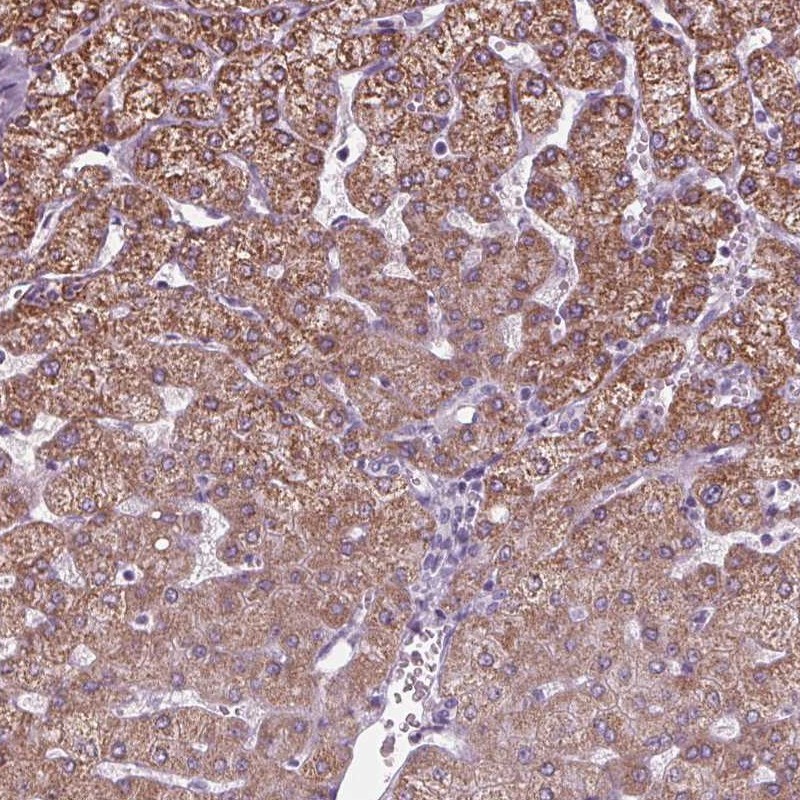

Immunohistochemical staining of human liver shows moderate cytoplasmic positivity in hepatocytes.